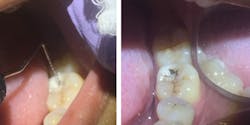

Silver diamine fluoride is applied to occlusal decay.